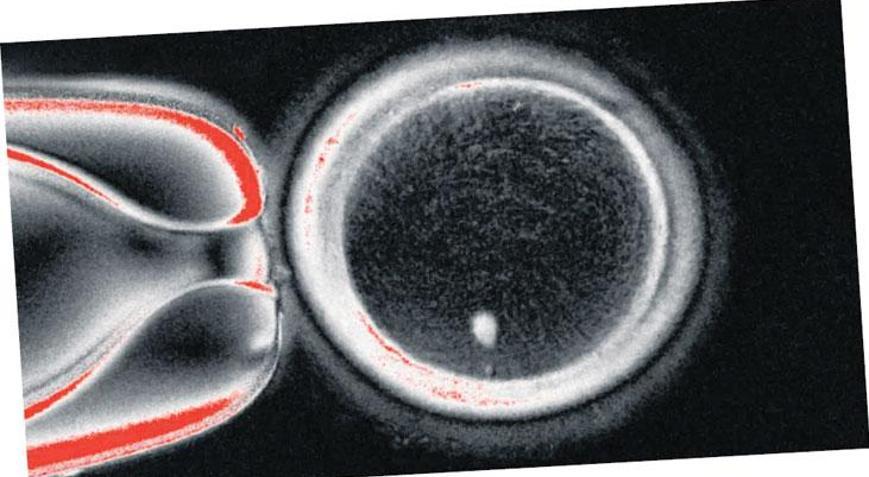

ABD’de kısırlığa çare olarak yeni bir yöntem geliştirildi. Oregon Sağlık ve Bilim Üniversitesi’nde insanların deri hücrelerinden alınan DNA’ların işlemden geçirilmesiyle yumurtalar elde edildi. In vitro gametogenez (IVG) denilen bu yöntemle “oosit” denilen 82 adet yumurta oluşturuldu. Bu yumurtalar, tüp bebek yöntemiyle (IVF) laboratuvarda spermlerle döllendirildi. Böylece yaşamın başlangıcı olan embriyolar oluştu. Altı gün sonra embriyoların yüzde dokuzu, IVF işlemi için rahime transfer edilebilecek kadar gelişti. Ancak embriyolarda bir dizi anormallik görülünce deney sonlandırıldı. Çalışmada, 1996’da Dolly adlı koyunun klonlanmasında kullanılan yöntemden faydalanıldı. Araştırmacılar, bu teknikle vücuttaki hemen her hücrenin çocuk dünyaya getirmek için kullanılabileceğini söyledi. Deneyler devam ederken yöntemin gerçek hayatta uygulanmasının 10 yılı bulabileceği belirtildi.

Yeni geliştirilmekte olan yöntemle yaşlılık veya hastalıktan kaynaklanan kısırlığın üstesinden gelinebileceği bildirildi. Çalışmayı yapan ABD’deki Oregon Sağlık ve Bilim Üniversitesi Embriyonik Hücre Merkezi Direktörü Prof. Shoukhrat Mitalipov, “İmkansız sanılan bir şeyi başardık” dedi. Mitalipov, “Hedefimiz yöntemi kusursuz hale getirmek. Geleceğin bu yönde ilerleyeceğini düşünüyorum. Çünkü çocuk sahibi olamayanların sayısı artıyor. In vitro gametogenez denilen bu teknoloji, vücut dışında sperm ve yumurta üretmeyi hedefliyor. Amaç kullanabilecekleri spermleri veya yumurtaları olmayan kişilerin çocuk sahibi olmasını sağlamaktır” diye konuştu.